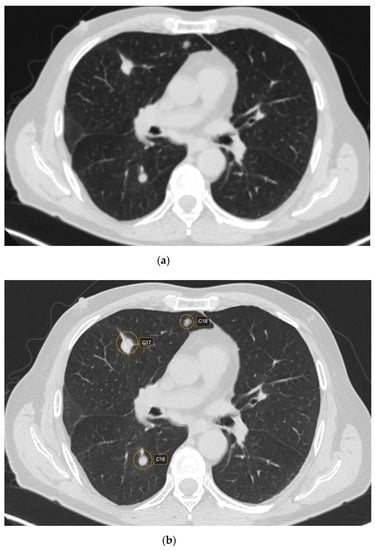

Out of 481 possible nodules detected by CAD, 12 were rejected by the radiologist, being considered false positive. The main reasons for false positives included fibrosis—five (41.66%) nodules; broncho-vascular structures—six (50%) nodules; and artifacts due to respiratory motions—one (8.33%) nodule. The majority of the false positive nodules were located in the parahilar area—seven (58.33%) nodules. Regarding the size of the false positive nodules, four (33.33%) had <6 mm, seven (58.33%) had between 6 and 8mm and one (8.33%) had > 8 mm (Figure 1 and Figure 2).

Figure 2. CT scan in lung window depicting lung nodules on raw CT images (a) versus marked CT images using CAD (b).